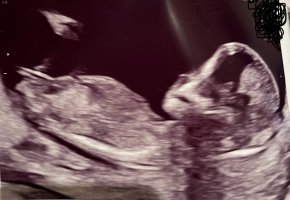

Dette er en tydelig jente! Ultralyd er jo snitt av kroppen, det betyr at ikke alt er synlig samtidig og da kan jo f.eks deler navlestreng eller lårbein eller en hånd som stikker ned se ut som noe er mellom beina litt her og der. Hvis du er 14 uker så hadde du sett en ganske tydelig penis nå. Hos gutter ser man gjerne at blæren er mye lavere hvis penis ikke skulle blitt med på bilde.Mulig å se noe her? Syntes jeg så en tydelig snopp på ultralyden, men jordmoren sa hun holdt en finger på jenteMålt til 14+0

Var på ul i dag.ÅååDette er en tydelig jente! Ultralyd er jo snitt av kroppen, det betyr at ikke alt er synlig samtidig og da kan jo f.eks deler navlestreng eller lårbein eller en hånd som stikker ned se ut som noe er mellom beina litt her og der. Hvis du er 14 uker så hadde du sett en ganske tydelig penis nå. Hos gutter ser man gjerne at blæren er mye lavere hvis penis ikke skulle blitt med på bilde.

Jente. Min jente så lik ut sistMulig å se noe her? Syntes jeg så en tydelig snopp på ultralyden, men jordmoren sa hun holdt en finger på jenteMålt til 14+0

Det er 100% jente. Du kan kjøpe inn kjoler, for du kommer aldri til å få høre gutt på neste ultralyd.Mulig å se noe her? Syntes jeg så en tydelig snopp på ultralyden, men jordmoren sa hun holdt en finger på jenteMålt til 14+0